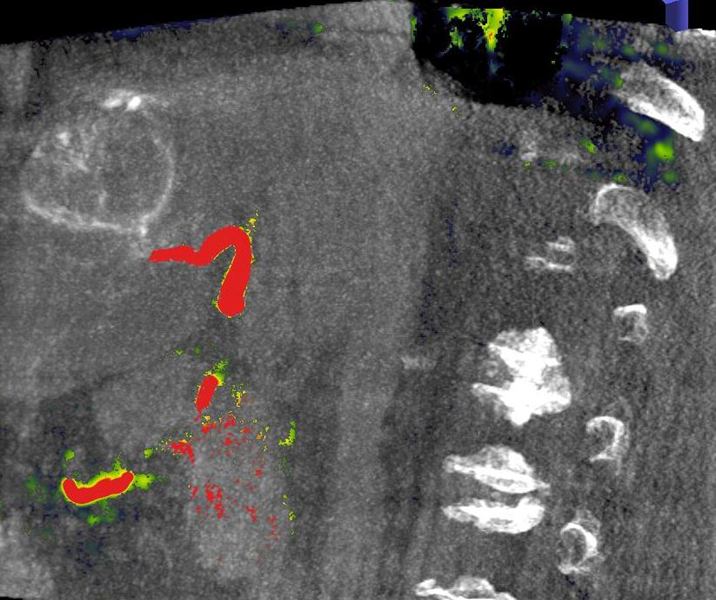

Die Mikrowellenablation (MWA) ist ein minimal-invasives Verfahren zur perkutanen minimalinvasiven Tumortherapie, das in den letzten Jahren zunehmend an Bedeutung gewonnen hat. Wie bei der der Radiofrequenzablation wird hierzu unter CT- oder MRT Kontrolle eine spezielle Nadel durch die Haut in den Tumor geschoben. An der Spitze der Nadel wird durch elektromagnetische Mikrowellen Hitze erzeugt. Im Gegensatz zur RFA beruht die MWA nicht auf einem elektrischen Stromfluss, wodurch bei der MWA höhere Temperaturen erreicht werden können, so können z.T. schneller und auch größere Ablationszonen erreicht werden, die weniger von umgebenden Blutgefäßen beeinflusst werden. Die Entscheidung, welches Ablationsverfahren für einen Patienten geeigneter ist, wird individuell je nach Lage und Größe des Tumors getroffen. Die Eingriffe werden je nach Tumorlage und Größe unter lokaler Betäubung oder in Vollnarkose durchgeführt. Einsatzbereiche des Verfahrens sind u.a. Tumore der Leber, Niere und der Lunge.